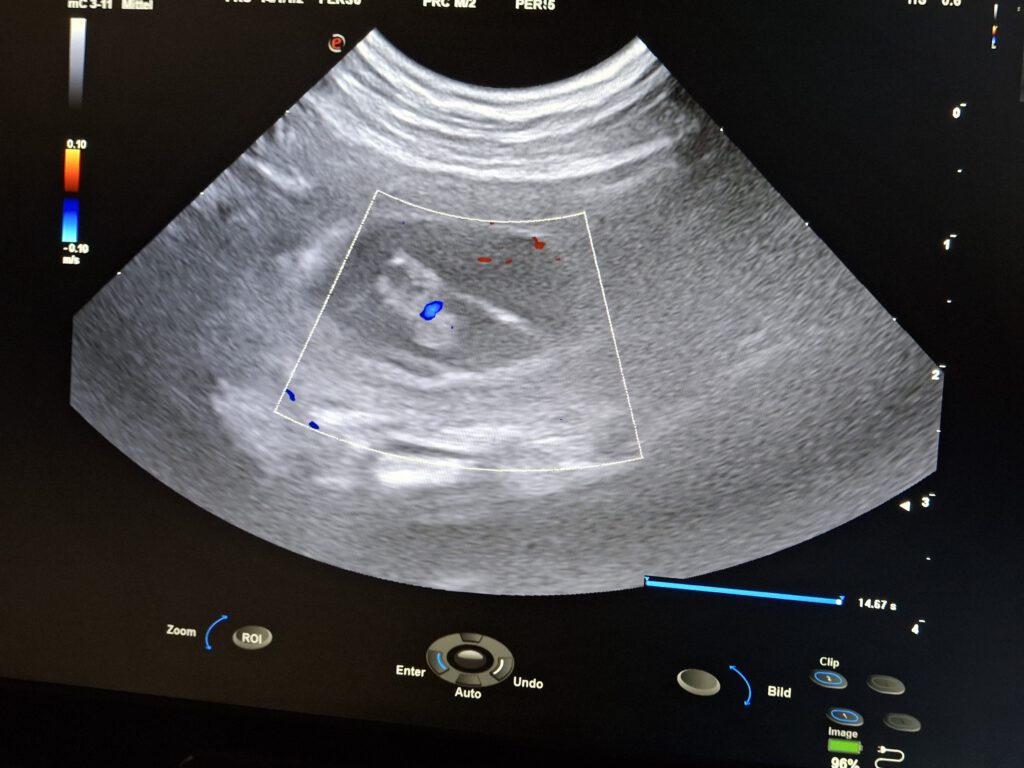

Gestern hat uns unsere Cassy ihr Geheimnis verraten. Wir waren gestern beim Ultraschall bei Fr Dr Mörke in Dortmund Sie konnte mehere Fruchteinlagen sehen. Cassy ist tragend und wenn alles gut verläuft wird unsere G- Wurf ca am 23 April 2026 landen.